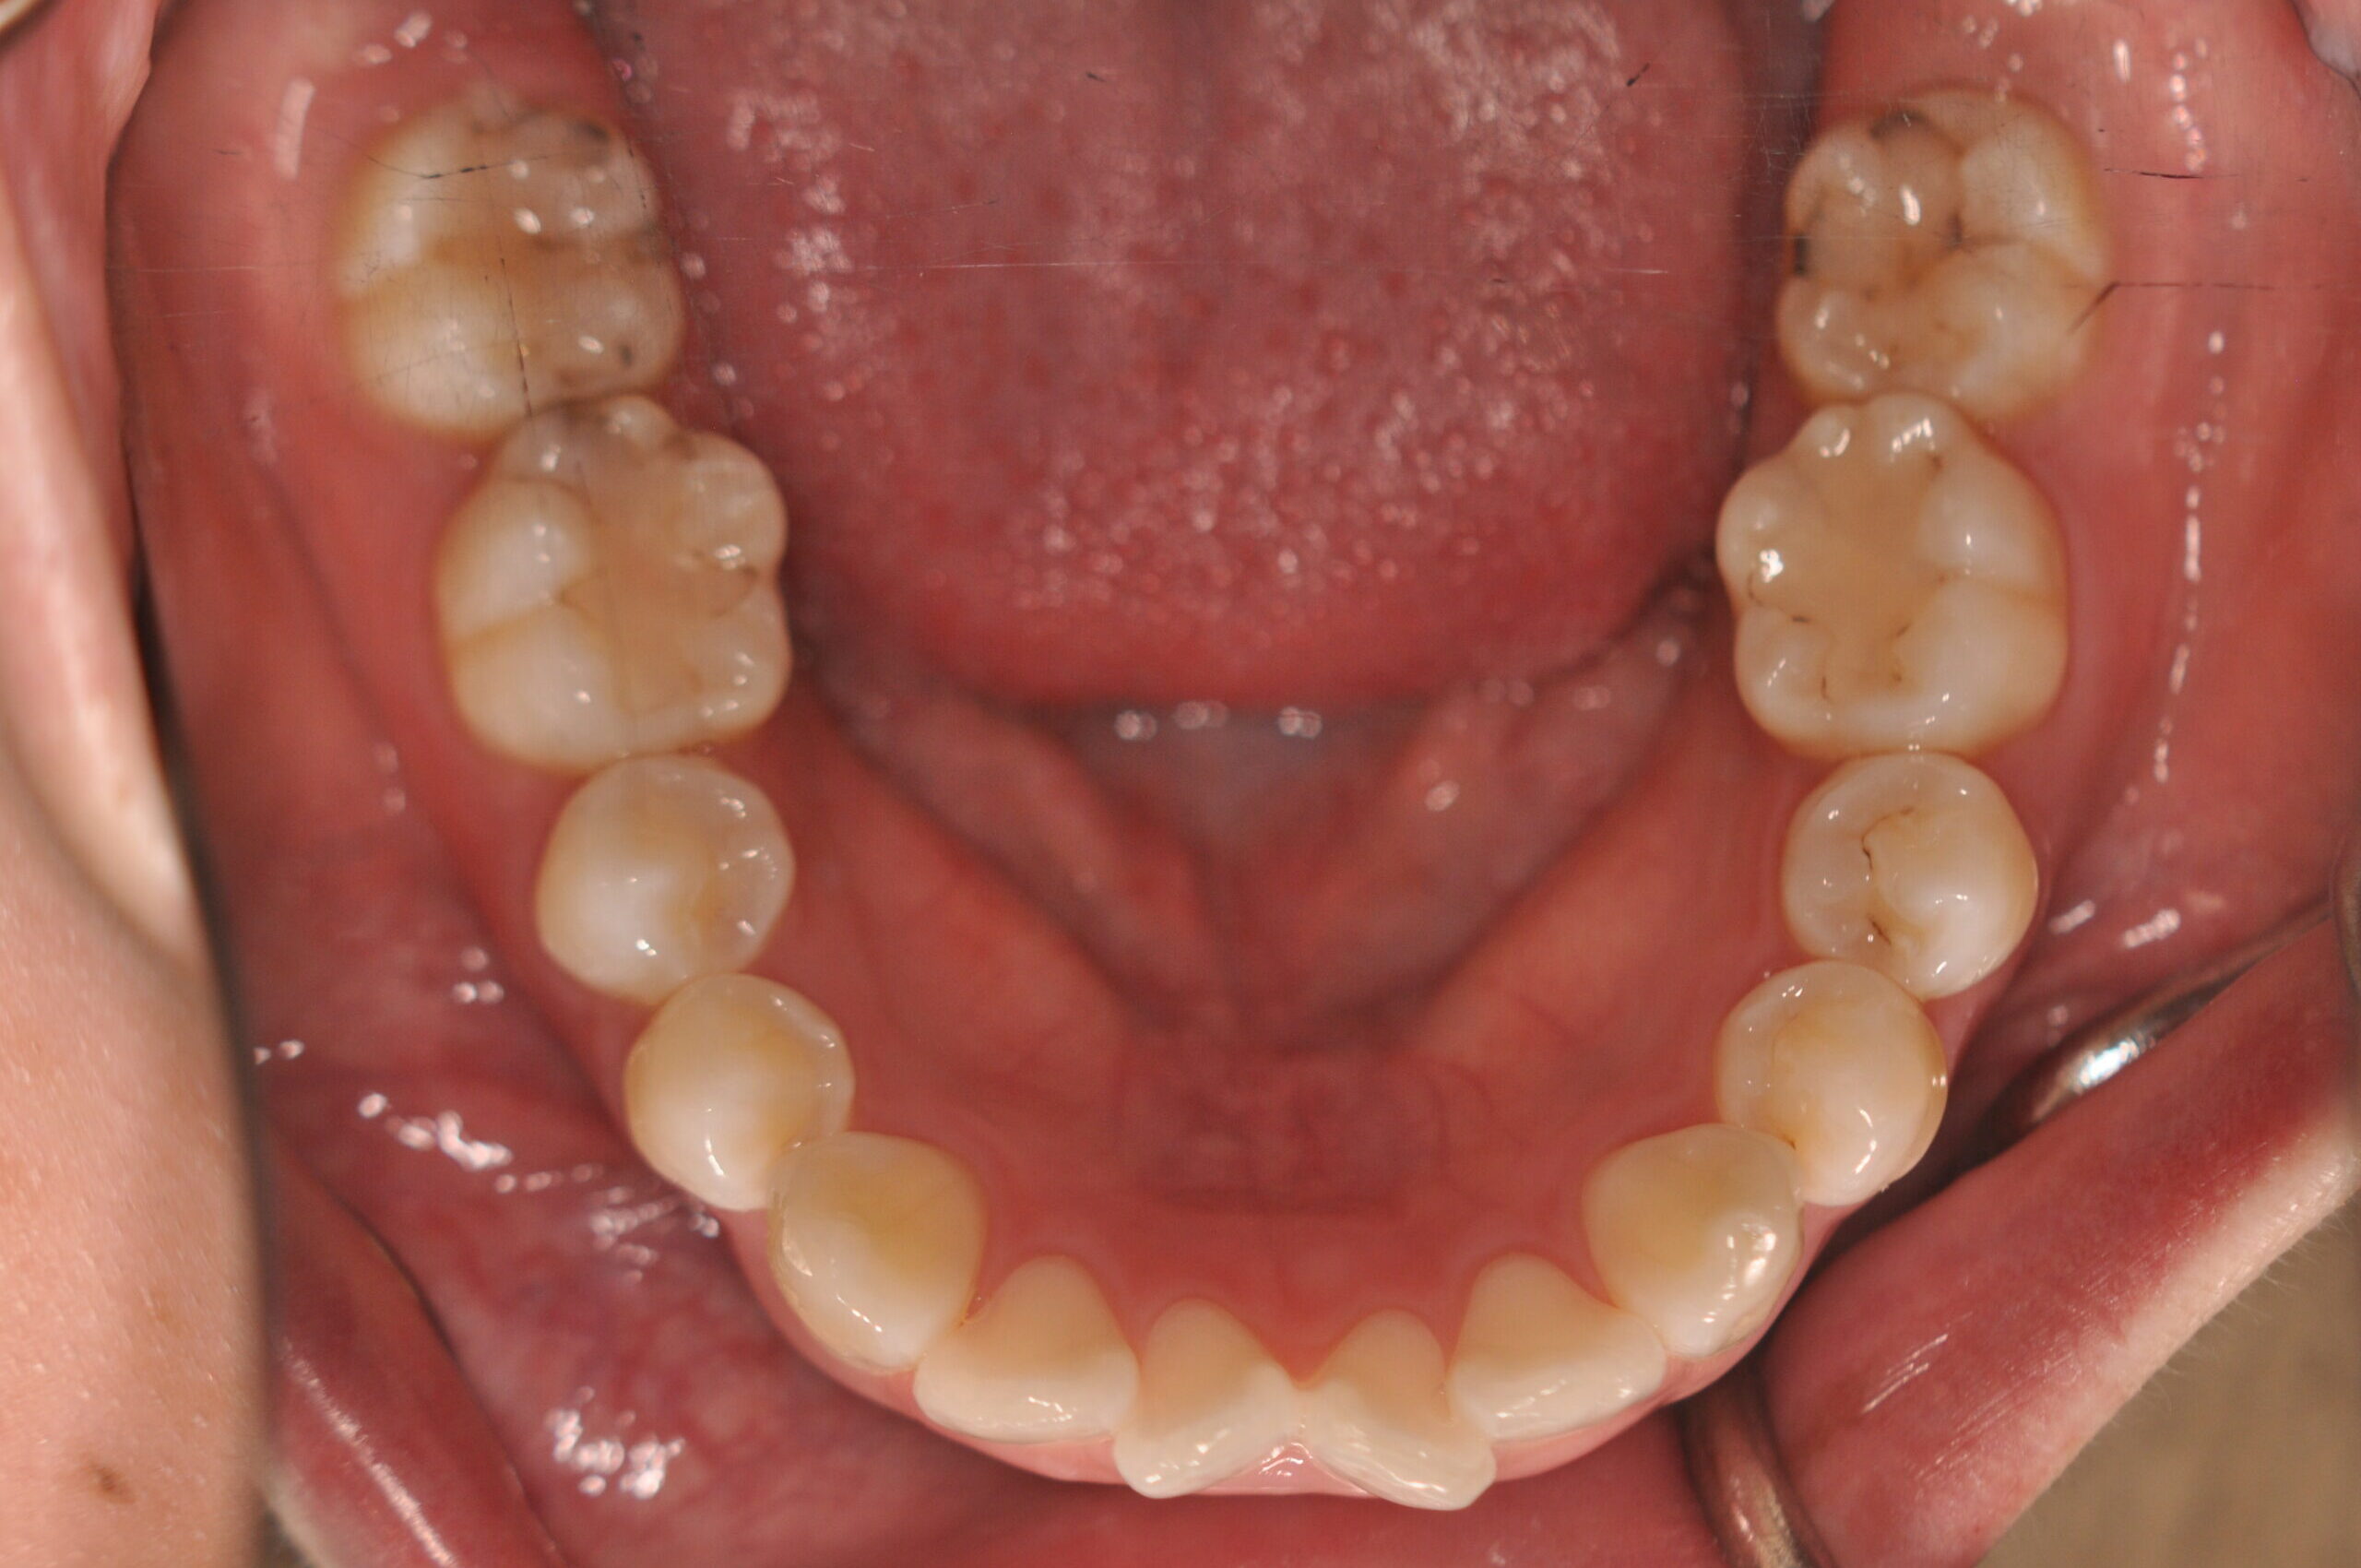

| 治療内容の詳細 | 初診時29歳の女性で、出っ歯を気にされ来院されました。 検査の結果、上顎前突を伴うアングルⅡ級1類不正咬合と診断しました。 治療としては、上顎左右第1小臼歯および下顎左右第2小臼歯をして、セルフライゲーションブラケット装置(デーモンシステム)で歯の配列を行いました。 同時に顎間ゴムにて咬合関係の改善を行いました。 この際、上顎に歯科矯正用アンカースクリューを設置し上顎前歯部後退時の土台としました。 治療期間は、2年6ヶ月でした。 |